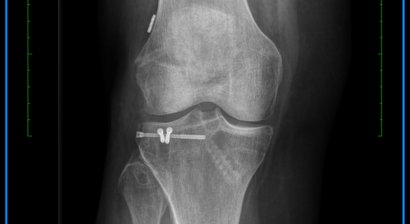

In meiner Privatordination biete ich Ihnen anhand einer ausführlichen klinischen Untersuchung sowie präziser Beurteilung der Bildgebenden Diagnostik (Röntgen, CT, MRT) eine ausführliche Erklärung Ihrer Verletzung/Diagnose die Sie verstehen!

Im Speziellen betrifft dies die Diagnose und Behandlung von akuten Verletzungen oder chronischen Schäden des Kniegelenkes. Dazu gehören insbesondere die Therapie der instabilen Kniescheibe sowie Behandlung von Bandverletzungen und Achskorrekturen bei verschiedenen Indikationen.

* Therapie der instabilen Kniescheibe (Patellaluxation), insbesondere komplexe Instabilität (Trochleadysplasie)

* Behandlung von akuten Tibiakopffrakturen oder deren Folgen